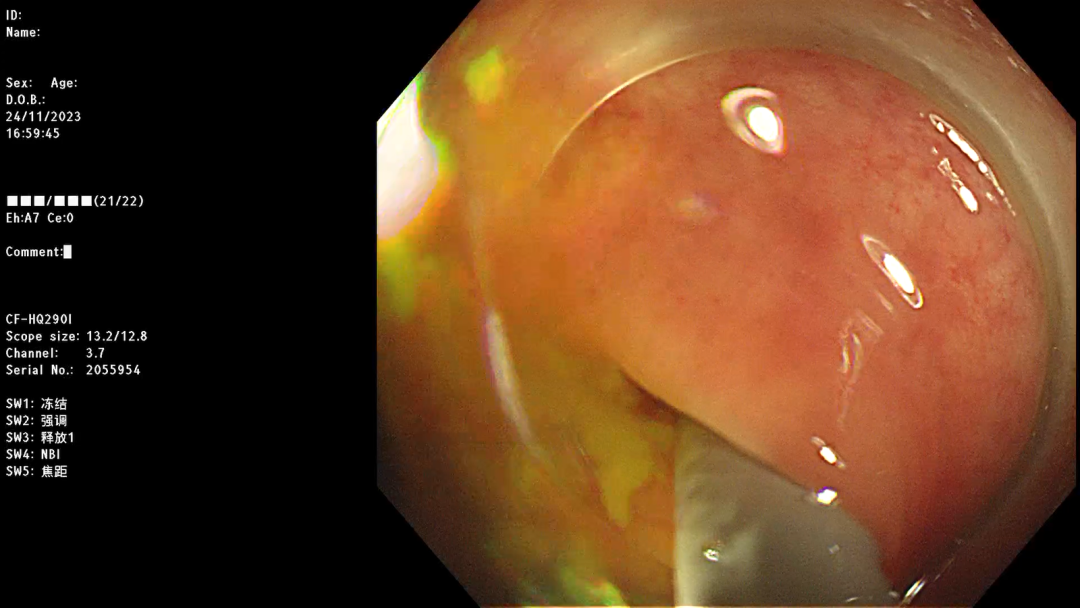

冲洗干净后的阑尾腔